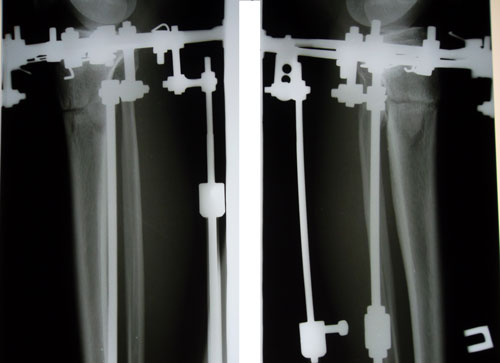

Рентген в 2 месяца.

Вложения

SAM_9288.JPG

SAM_9287.JPG

Здравствуйте, Жанна! Рентген выставлю завтра. Сращение идёт отлично, ось в норме, всё у Вас хорошо!